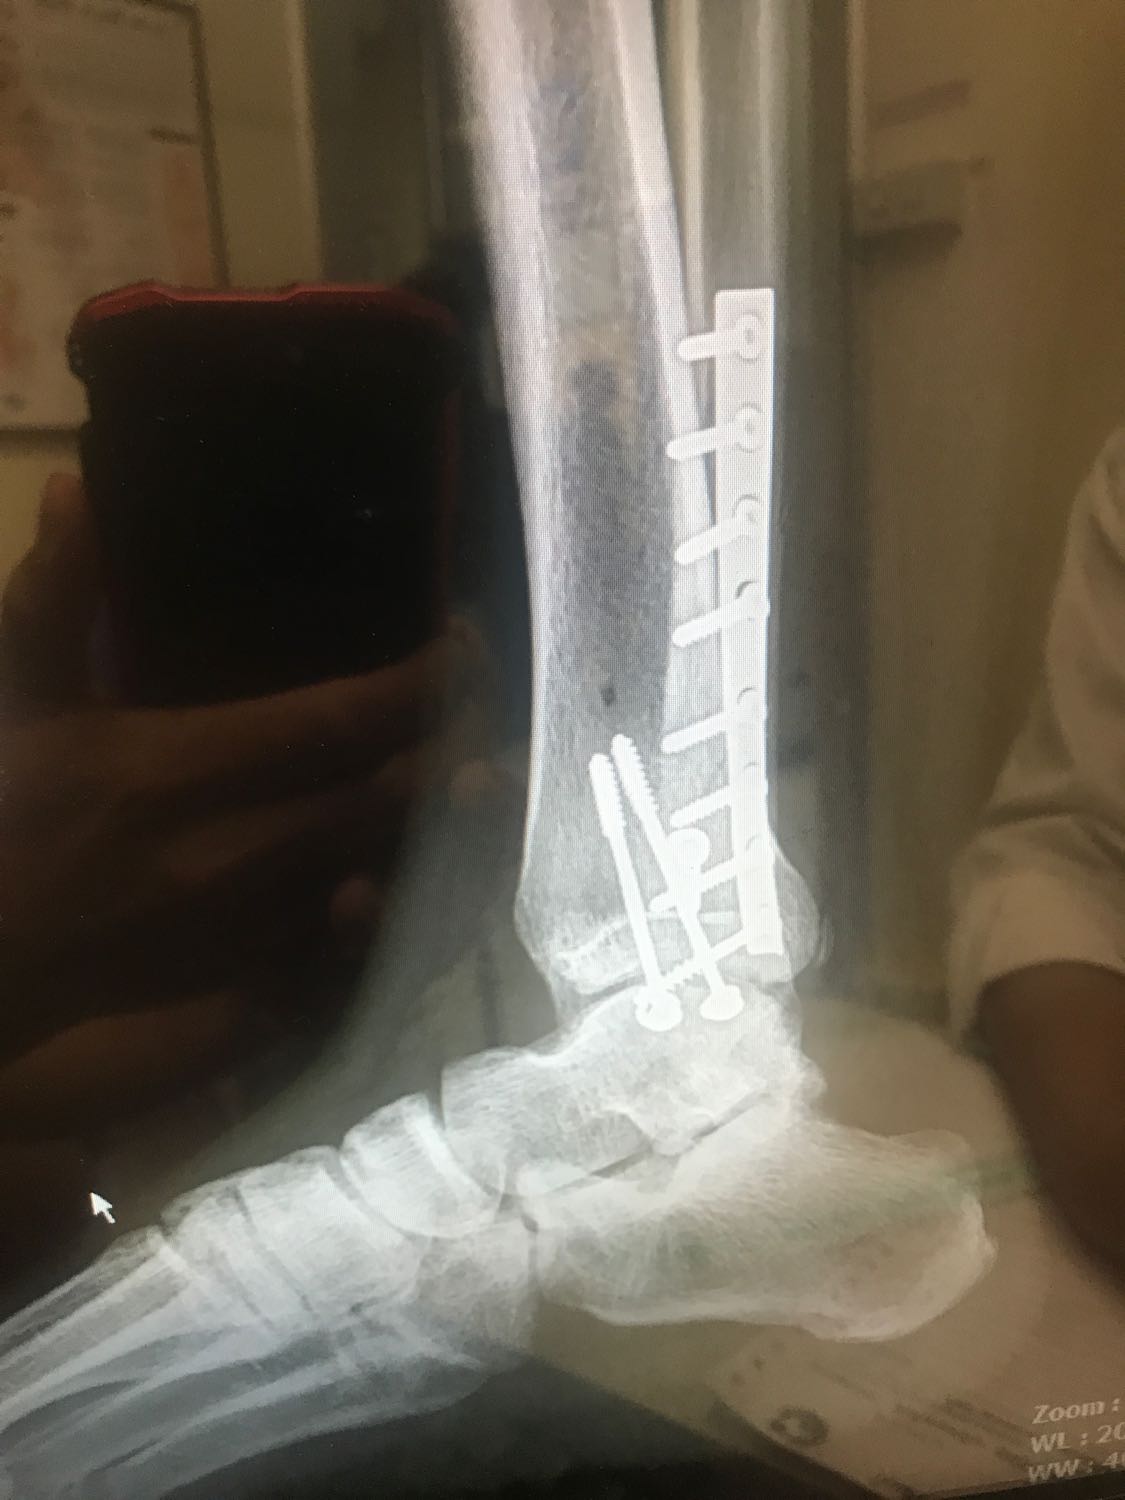

เท่าที่ดูจากภาพ ผมเดาว่า ..

๑. กระดูกข้อเท้า ( talus bone ) มีสีขาวมากกว่าปกติ ผิวขรุขระ ซึ่ง " เดาว่า " อาจเกิดจาก กระดูกเสื่อม ยุบ (talus bone avascular necrosis)

๒. ซึ่งทำให้เกิดอาการ บวม ปวด ข้อเท้าได้ .... ( ส่วนเรื่อง ชา อาจเกี่ยว หรือ ไม่เกี่ยวก็ได้ )

๓. กระดูกติดแล้ว ถ้าจำเป็น จะผ่าเอาเหล็กออก ก็ได้

ู๔. แนะนำไปพบแพทย์ที่ผ่าตัดให้ หรือ ไปพบหมอกระดูกและข้อ ท่านอื่น เพื่อตรวจ วินิจฉัย และ ปรึกษาแนวทางการรักษา

ภาพ talus bone avascular necrosis

ขาหักที่ข้อเท้า ผ่าใส่เหล็ก แล้วชาที่ปลายเท้านิ้วนาง

1.ชาที่ปลายนิ้วชี้(เกิดได้อาทิตย์นึ่งแล้ว)

2.มีอาการบวมบริเวณที่ข้อเท้า(เวลาทำงานจะบวมและปวดเป็นพิเศษ)

(รูปถ่ายจากแผ่นเอ็กสเล)